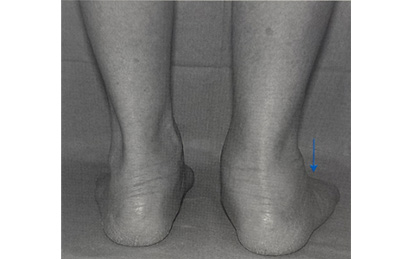

診察所見では、足関節の内側の後脛骨筋の断裂があるかを触れる事や、患者さんを後ろ向きにしたときに特徴的な、too many toes signを確認します。

画像参考:日本足の外科学会監修 足の外科テキスト、南江堂 p171

左が正常です。踵の骨が外反といって傾いており、外側の足趾が多く後ろから確認できる扁平足の特徴的なサインです。